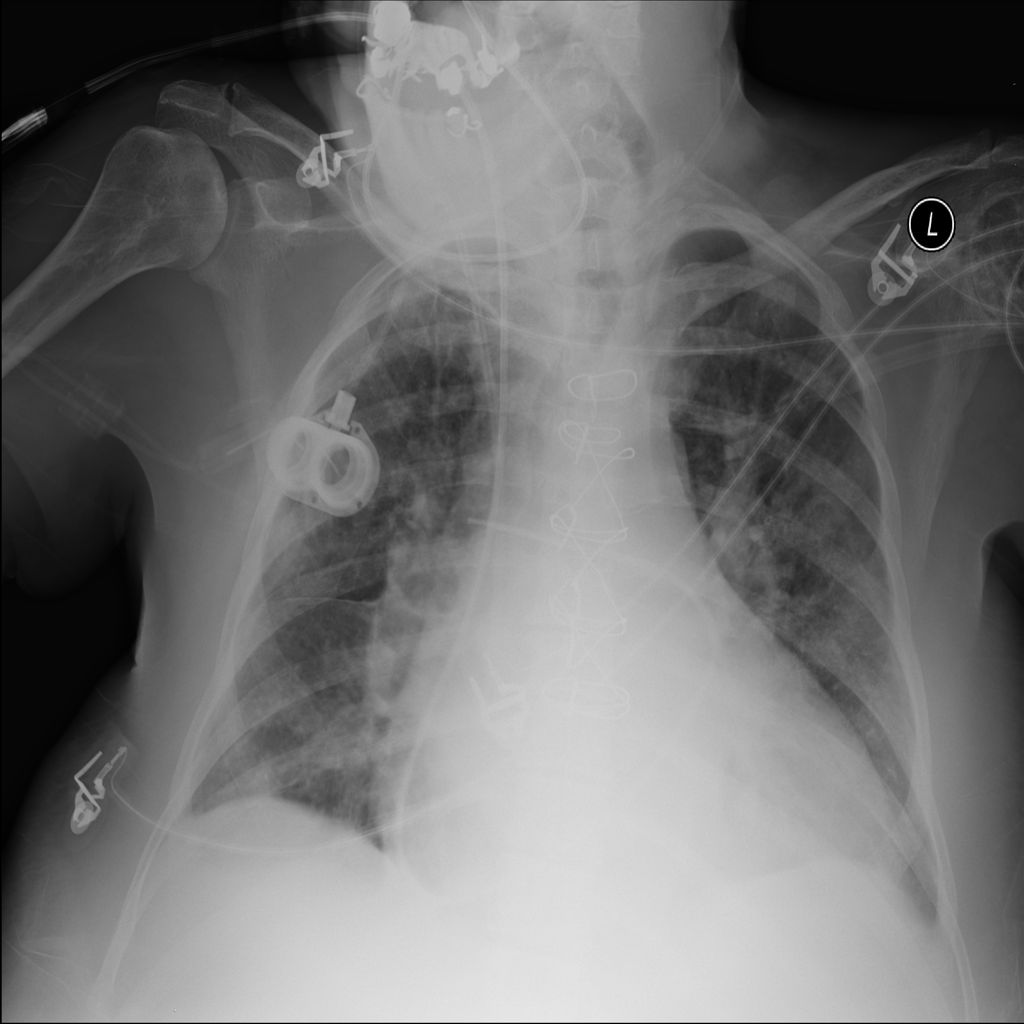

PAT-F3E7 · IMG-000Cardiomegaly

PAT-F3E7 · IMG-000

PA